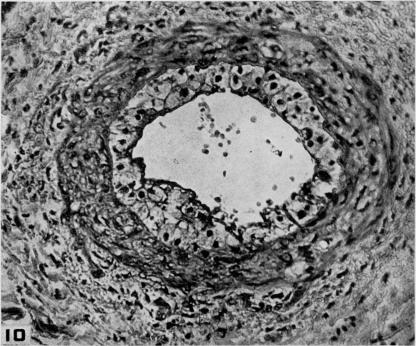

Studies on the pathogenesis of vascular disease; the effect of intravenous egg-yolk emulsions on inflammatory lesions of the aorta and coronary arteries of dogs.

Yale J Biol Med. 1956 Sep;29(1):9-22.